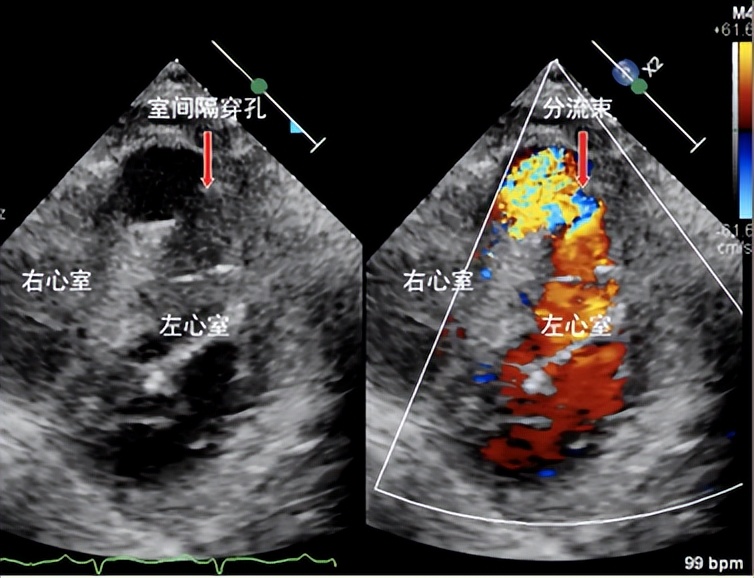

术前心脏彩超显示室间隔近心尖处穿孔及左向右分流束

患者为92岁女性,入院前1周突发胸骨后闷痛,因胸痛程度不剧烈且症状自行缓解,误以为是胃肠道疾病,未予重视;后逐渐出现恶心、四肢乏力、气促、端坐呼吸等症状,由家属送至我院急诊科。急诊行心电图提示患者前壁心肌梗死,进一步完善心脏彩超见室间隔心尖段变薄、搏幅减低,探及大小约19mm回声失落,合并室间隔穿孔。